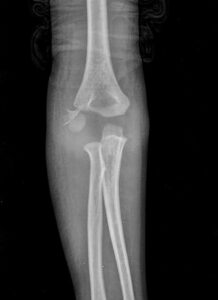

Grafi kararı alınan hastada Antero-Posterior(AP) ve Lateral grafi standart olarak ilk yapılan görüntülemelerdir.

AP grafi çekilirken dirsek tam ekstansiyonda ve önkol supinasyonda olmalı.

Uygun bir lateral grafi çekimi için dikkat edilmesi gereken noktalar ise; dirsek 90° fleksiyonda, ön kol supinasyonda, humerus ve önkol çekim yapılan kasete temas etmeli yani omuz dirsekten daha yukarıda olmamalıdır.